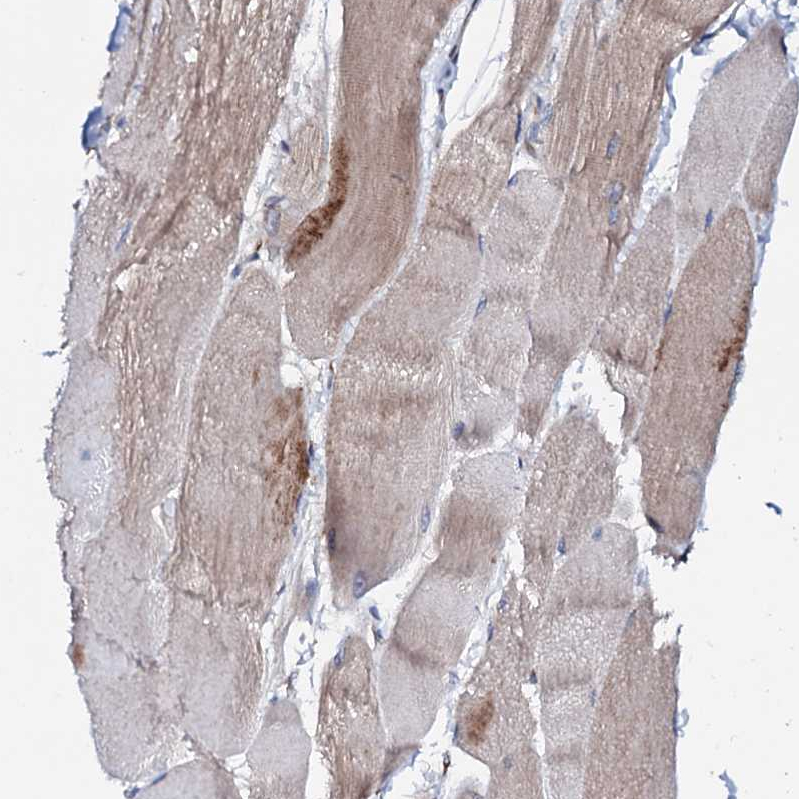

Immunohistochemistry analysis in human placenta and skeletal muscle tissues using HPA039494 antibody. Corresponding P2RX4 RNA-seq data are presented for the same tissues.